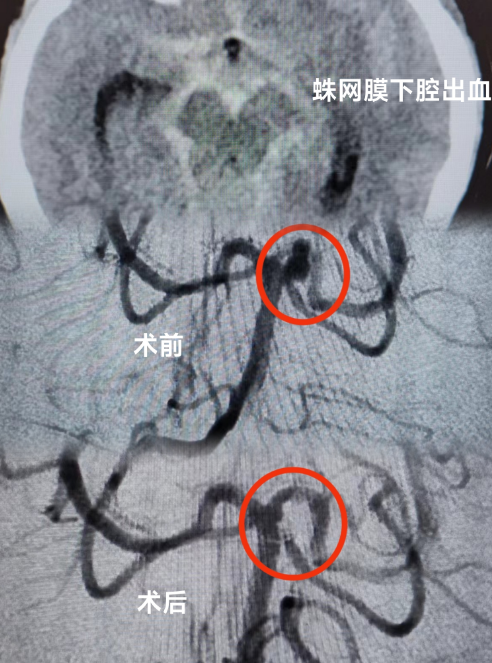

当天,患者被送到急诊科时,医生为她紧急安排头颅CT检查,发现患者有蛛网膜下腔出血的情况。蛛网膜下腔出血通常病情比较严重,可诱发脑血管痉挛,进而继发出现脑梗死,危害患者生命。为了帮助患者尽快脱离危险,急诊科立即联系了神经外科、重症医学科及心血管内科当班医生进行联合会诊。

皇冠足球投注网 多学科专家团队结合患者检查结果,认真分析患者病情,判断患者动脉瘤破裂出血可能性大,同时合并有急性冠脉综合征,不排除急性心梗的可能。考虑到患者病情的危重性及复杂性,专家团队建议患者入住重症监护病房(ICU),紧接着由神经外科医师团队运用神经介入技术为患者进行脑血管疾病诊治,同时神经外科医师与心血管内科介入医师通力合作,排查了心脏冠脉相关疾病。期间,麻醉科、重症医学科医师团队也全程为患者保驾护航,排查手术各种风险。

手术历经约3个小时,专家团队排除万难,为患者完成了全脑血管、冠脉造影术,以及颅内动脉瘤介入栓塞术手术,术后患者恢复良好。